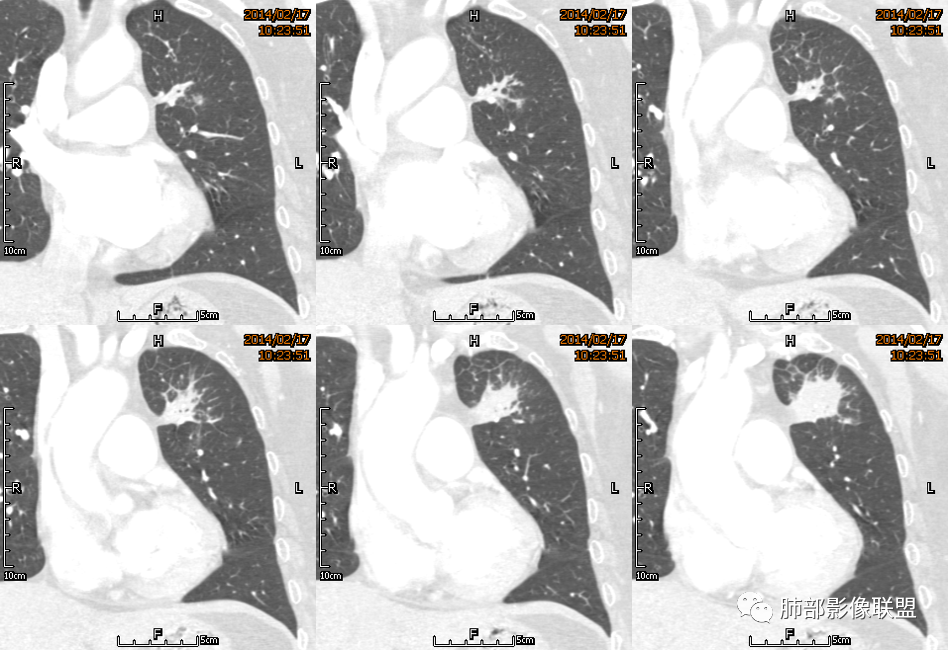

薏米: 老年女性,急性起病,咳嗽,咳痰,咯血,白细胞低,胸部CT提示左肺上叶可见一团块样密度增高影,边缘平直,部分略有膨隆,内可见支气管进入后截断,小的空洞,血管造影,坏死,明显强化,周边可见少许索条,考虑炎性病变,肺脓肿可能。鉴别结核,隐球菌。

一切∮随缘: 定位:肺内,左肺上叶肿块,呈长条状,平行血管束生长,边缘分叶,平扫密度均匀,增强后不均匀强化,可见低密度坏死,近段支气管及血管穿行病灶内,远端堵塞支气管,血管似有破坏,周围散在点状小结节,及纤维索条影,考虑恶性:腺癌,类癌,淋巴瘤。鉴别结核及隐球菌。

红星: 老年女性,咳嗽咳痰10天,痰中带血4天。左肺上叶前段胸膜下肿块影,沿支气管方向走行以膨胀生长为主,局部有收缩改变,支气管血管绝断,中间有小片状的坏死及小的空洞影,增强扫描病灶明显的强化,病灶周围网格状的小叶间隔增厚。拟左肺上叶前段浸润型腺癌并癌性淋巴管炎。鉴别诊断结核肉芽肿。

秦化君: 左肺上叶前段胸膜下软组织密度肿块影,边缘清晰,部分边缘膨隆,纵隔缘弧形内凹,脂肪界面清晰。肿块中心密度减低,支气管进入病灶后截断,似有扩张表现,病灶周围可见小叶间隔增厚,斑片影,近端支气管似管壁增厚。增强后明显强化,中心见低密度区。考虑:1.肉芽肿性炎?2.IMT?3.淋巴瘤?

傅昌瑜: 老年女性,咳嗽咳痰10天,痰中带血4天。左肺上叶前段胸膜下肿块影,沿支气管方向走行,膨胀生长为主,局部边缘似有收缩改变,中间有小片状的坏死,支气管进入,增强扫描病灶明显的强化,血管走形较自然(血管漂浮征?),病灶周围网格状的小叶间隔增厚。考虑淋巴瘤可能性大,注意鉴别炎性肉芽肿及肺腺癌。

水晶石头: 患者老年女性,咳嗽咳痰10天,痰中带血4天余。查血常规白细胞低;肿瘤标志物、凝血功能正常;血生化:蛋白低;C反应蛋白、血沉稍升高。胸部CT:左肺上叶前段胸膜下沿气管支气管走形肿块影,长轴与胸膜平行,见分叶、毛刺、支气管截断、空泡征象。增强明显强化,且见血管造影征及病灶内小灶低密度坏死区。左肺上叶尖后段见一结节灶。综合考虑恶性病变可能大,腺癌或淋巴瘤可能。鉴别诊断肺脓肿。

尘缘: 老年女性,咳嗽咳痰10天,痰中带血4天,白细胞及中性粒明显减低,轻度贫血。影像表现:左上叶肿块,边缘膨隆,局部平直,支气管稍扩张,进入后远端堵塞,内见小空洞及不规则坏死区,增强后强化明显,坏死边界较清,并见环状强化区,内部血管走行自然,周围见小叶间隔增厚呈大网格征。初步诊断:慢性炎性伴脓肿形成及肉芽组织增生。鉴别淋巴瘤及腺癌,先抗炎治疗后复查或直接穿刺明确。

张延军: 左肺上叶前段软组织影,偏下缘见充气支气管,部分支气管壁与肿块近端增厚狭窄。实性部分见血管穿行,边缘平直并局限性凹陷,增强扫描内见斑片状低密度区,界不清,实性部分中度强化,病变外宽内窄,基底贴于胸壁,周围肺组织内见条片状密度增高影,考虑炎性,结核?腺癌待排。

毛勤香: 老年女性,左肺上叶胸膜下肿块,部分膨隆部分收缩,边缘毛糙模糊,周围少许索片状影,小叶间隔增粗,支气管进入后截断,增强扫描明显不均匀强化,内低密度区无明显强化,血管走行尚可,首先考虑感染性变并脓肿形成,鉴别淋巴瘤,建议抗炎后复查。

宇宙星空: 外大内小,近端支气管壁增厚,爬树征,内部坏死不均匀,都比较典型了。支持结核,鉴别炎性肉芽肿、慢性脓肿。

王崇军: 老年女性,咳嗽咳痰10天,痰中带血4天。左肺上叶前段胸膜下 肿块影及段形态密度增高影,沿支气管方向走行,膨胀生长为主,局部有收缩改变,支气管进入并闭塞,中间有小片状的坏死及小的空洞影,空洞漂浮在坏死边缘,增强扫描病灶明显的强化,坏死边界清楚,似乎有轻度强化环,病灶周围网格状的小叶间隔增厚及小结节影,外侧胸膜呈糊墙改变。考虑为肺脓肿,这么大的病灶,竟然没有发烧,白细胞低,CPR轻度升高,均与脓肿不符,所以恶性待排,短期抗炎治疗后复查,病灶没有变化,脓肿就可以排除,恶性基本可以确定。

空格: 临床特点:老年女,血糖略高,低蛋白血症,白细胞低,提示有免疫下降的存在。机会性感染存在机会。黄浓痰一般常见于炎性病变,痰中带血则肿瘤多见,两厢pk,觉得黄脓痰胜,除非肿瘤继发感染一般不会黄脓痰。影像:一 、良性征像:1.病灶整体是个尖端指向肺门的三角形病灶;2.胸膜平直,胸膜外少量液体糊墙;3.支气管未见明显截断,内壁毛糙?4.近端支气管弥漫性增厚,结核脓痰咯出,看做引流支气管;5.多个层面病灶呈直边征,多角征,无明显分叶;6.病灶内坏死边缘光整,伴小气泡。小叶间隔增厚光滑锐利,无结节,不太像癌淋。二、恶性征像:部分层面向胸膜外突,略有占位效应。总体考虑感染性病灶,霉菌可能。结核抗体阴性,可以排除?

刘和林: 老年女性,咳嗽咳痰10天,痰中带血4天。左肺上叶前段胸膜下 肿块影,沿支气管方向走行,膨胀生长为主,局部边缘似有收缩改变,中间有小片状的坏死,坏死区内见小气泡,支气管进入、部分填充、部分末端稍显扩张,增强扫描病灶明显的强化,周围肺不干净,其上肺见小叶间隔增厚。肺癌、淋巴瘤、炎性肉芽肿?肺癌:支气管末端稍扩张,周围类似树芽征改变,不太符合。淋巴瘤:数个小气泡,明显强化,周围树芽征样改变,不太符合。

王武章: 灶内低密度,花环样强化,血管穿行漂浮,邻近胸膜并未广泛增厚也未牵拉但接触面脂肪密度略高且模糊。考虑IMT,鉴别慢性炎症相关的非特异性瘤样病变。

宽基底,附近胸膜增厚,边缘平直

支气管通畅

血管走形自然

坏死灶边界清附近卫星灶

2.左肺上叶前段胸膜下块状影,不规则呈“逗点样”延向肺门区,边界清楚,未见分叶、毛刺及张力,表面不规则棘突,状如“火焰”或“日冕”。相邻胸膜增厚,未见栽赃、卫星病灶。

3.病灶密度不均,中央坏死液化并见气泡影,支气管及血管贴边进入,较均匀环形强化(显示多层结构),未见明确壁结节。